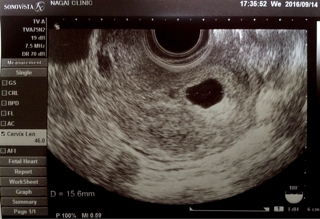

テーマ:不妊治療 ここ毎日更新していたブログを数日お休みしていました。 やはりメンタル的にきついのと、 夫が単身赴任中で余裕がない…というのが大きい感じ。 相変わらずつわりは続いていて、 出社もいつもより1時間くらい遅らせています。 基本的にずーっと二日酔いな感じ。 吐きはしないものの、ずーっと咽喉元ムカムカと頭痛とめまいがひどい感じ。 さて、タイトル通りですが… 今朝は夫が単身赴任先から帰ってきてくれていたので、 子どもの朝の支度は全て夫に任せ、遅くまで寝て...